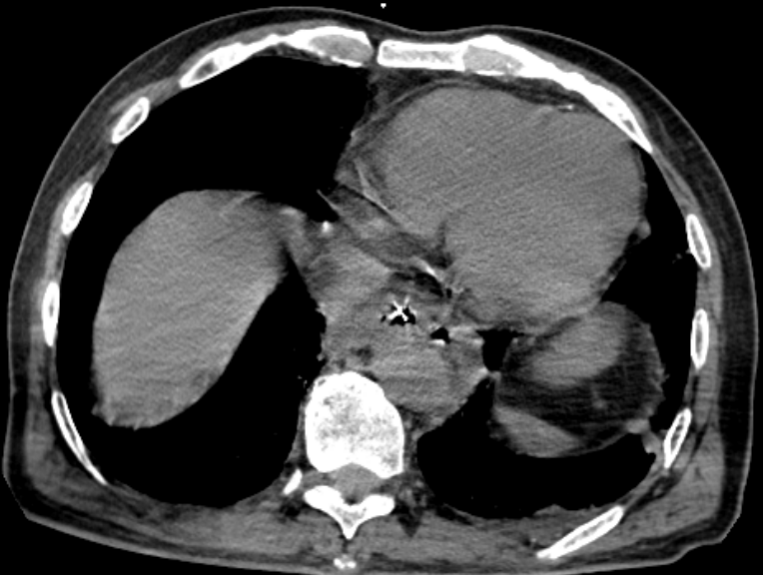

▲胸部CT可见食管内高密度异物及纵膈中低密度影

春节前的一个周末,一位老年男性患者就因为误食枣核3天就诊于北京市垂杨柳医院消化内科。消化内科医生谢俏在接诊后,根据患者病情,完善胸部CT检查,确认食管中段异物导致食管穿孔,同时已经出现了纵膈感染情况。患者血常规提示白细胞及C-反应蛋白明显升高,病情十分危重。谢俏立即联系医院胸外科医师赵云会诊,经学科讨论决定先行内镜下异物取出。

消化内科副主任医师黎俊及第二手术区副护士长刘晓静为患者进行急诊内镜下异物取出术。术中可见一枚枣核横跨在食管中段,其两端已经刺入食管左右壁,在食管穿孔局部进行吸引时,有大量脓液从穿孔处溢出。使用异物钳将枣核取出后,患者胸痛症状明显缓解。随后在内镜下放置鼻饲管及胃管进行引流,患者收入胸外科进一步诊治。在胸外科的细致诊治下,患者终于脱离险境,2周后复查胸部CT食管穿孔完全愈合出院。